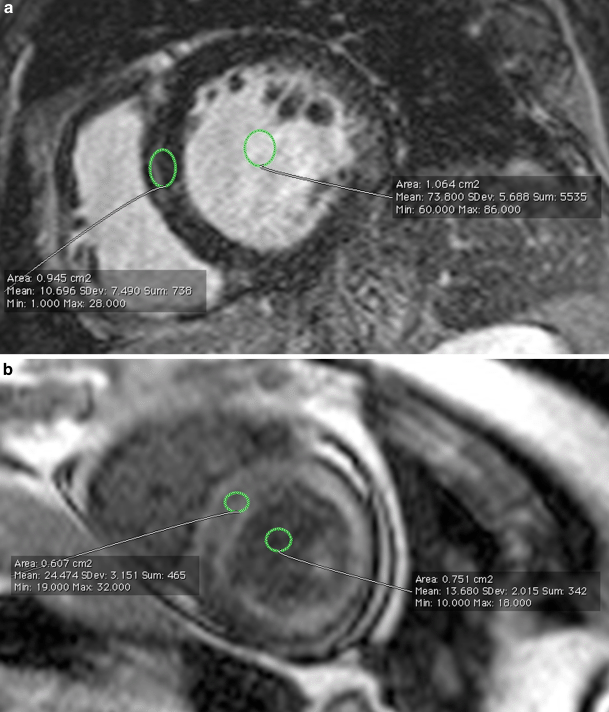

Example of blood/myocardial T1 ratio determination for semi-quantitative description of contrast washout. Both images are acquired with segmented inversion-recovery gradient echo sequence. a accelerated contrast washout. Blood T1 = 13 ms, myocardial T1 = 24 ms, blood/myocardial ratio = 0.5. b normal contrast washout. Blood T1 = 60 ms, myocardial T1 = 10 ms, blood/myocardial ratio = 6